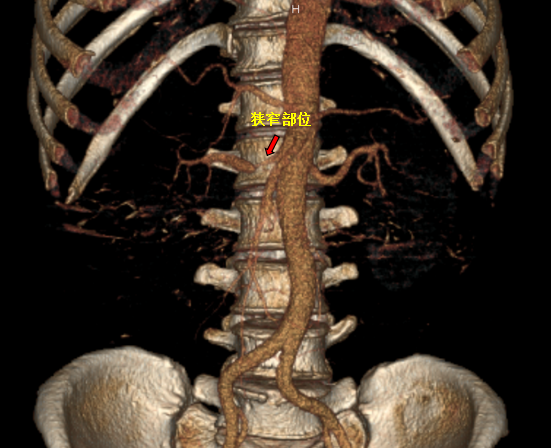

患者于4月9日上午送介入手术室行右肾动脉支架置入术。术中造影显示右肾动脉起始段明显狭窄,狭窄约90%,予置入肾动脉裸支架(7*19mm)后,造影显示右肾动脉狭窄解除,支架扩张良好,右肾灌注恢复。

a60c09d467d3b01e77d9133072a70a0.png

红色标记为支架置入后,狭窄解除